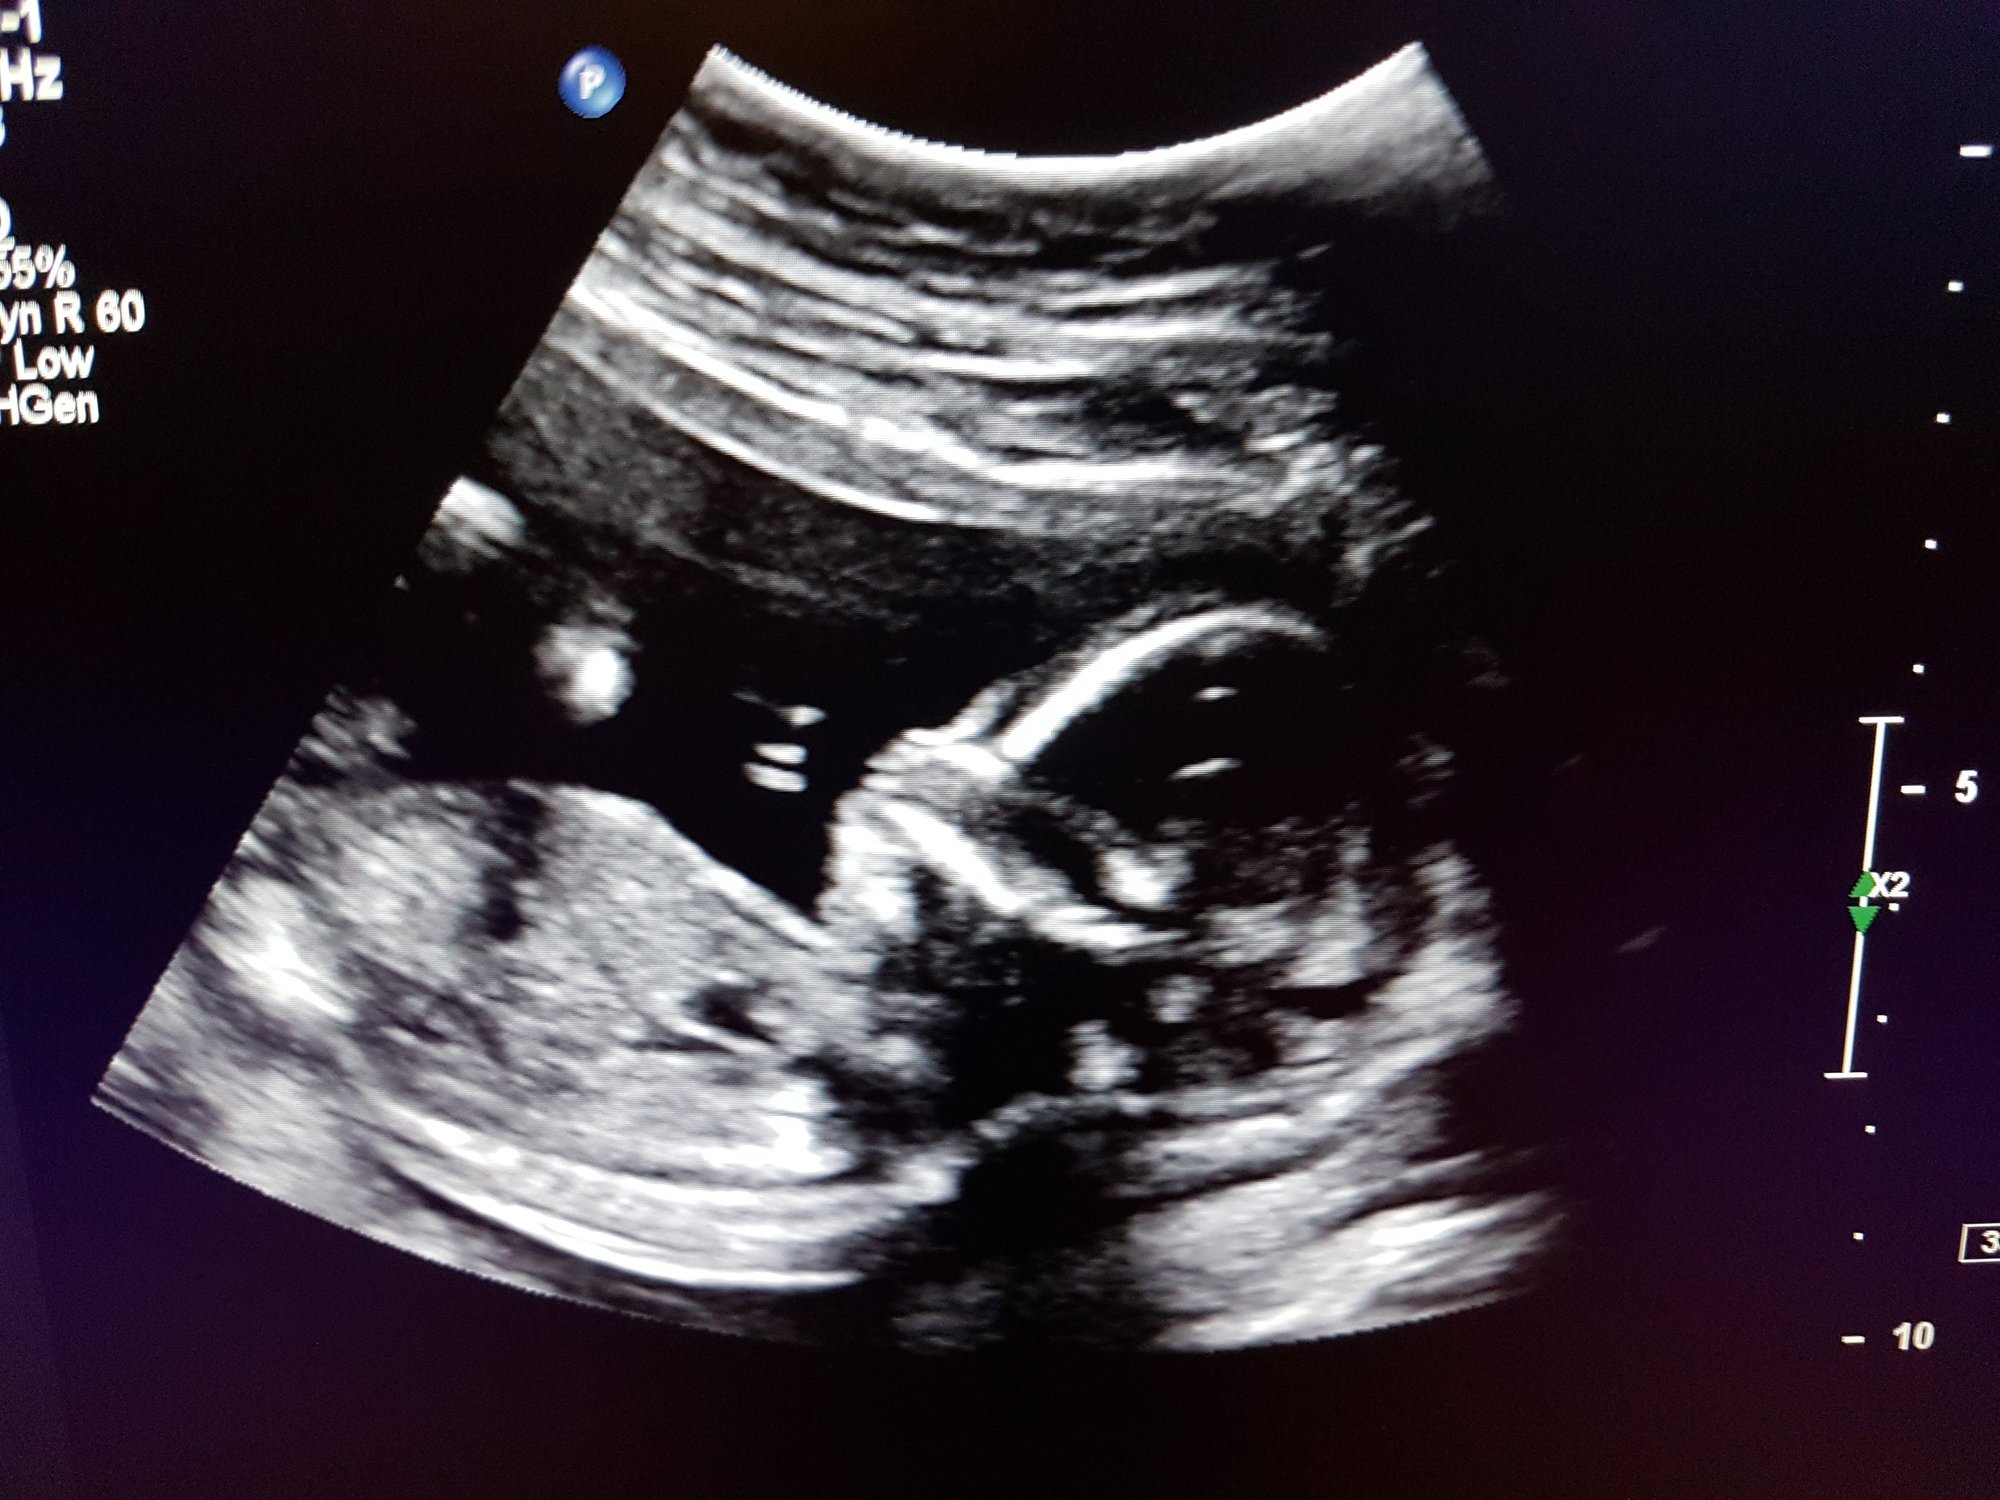

Little Dot is absolutely fine, doing perfect. Heartbeat of 167. Wiggling around and waving. Bleeding apparently might just be a *thing* for me throughout pregnancy. I can't express the amount of relief. Stop scaring your momma LO!!!